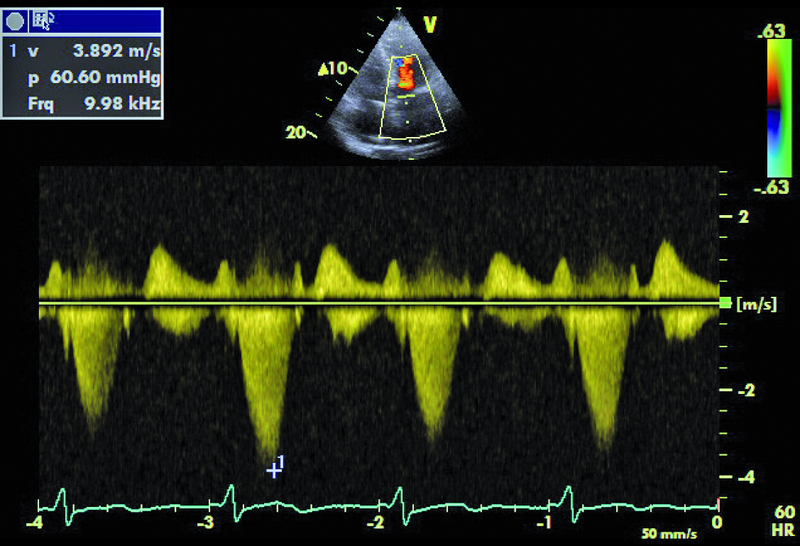

Kobieta, lat 55. Jakie patologie można rozpoznać na zamieszczonych rycinach?

3. Małe nadciśnienie płucne (ryc. 4).

5. Zawężanie drogi odpływu lewej komory (ryc. 5, 6).